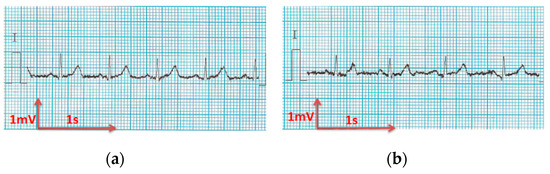

3.3.1. ECG Recorded by Portable Medical Device

- For all textile electrodes, ECG signals were recorded by a portable medical device as well as with a low-cost, Arduino-based open source device. Using portable medical devices, all electrocardiographic P, T waves, and QRS complexes were identifiable, despite higher contact impedance of PEDOT:PSS textile electrodes. Signal quality analysis by cardiologist showed that these textile electrodes, used in ambulatory conditions for heart monitoring, allow the detection of rhythmic disorders (Atrial Fibrillation, ventricular tachycardia, etc.) and conduction troubles (sinus dysfunction, atrioventricular block etc.), and can detect myocardial ischemia (ST segment underlining) in some cases. Such a system, integrated into garments, can be used in real-time and in continuous mode to monitor the user’s heart in a comfortable way, and to detect possible issues that, with additional analysis if needed, could be avoided, such as strokes. Regarding low-cost devices, assuming that high contact impedance between the skin and textile electrodes is the cause of no detectability or noise and severe distortion of cardiac waveforms, it was concluded that the amplifiers of the low-cost device are not appropriate to record ECG of our developed PEDOT:PSS textile electrodes, and also, that of commercial silver-plated electrodes. Textile electrodes inherently provide high contact skin-electrode impedance because the ECG recording is based only on natural skin moisture and perspiration and without any added gel. Therefore, compatible recording amplifiers with high input impedance are required to compensate for the high contact impedance skin-electrode, which is related to the low mobility of ions across the highly-resistant stratum corneum layer of the skin that causes weak conductivity between the electrodes and the skin.